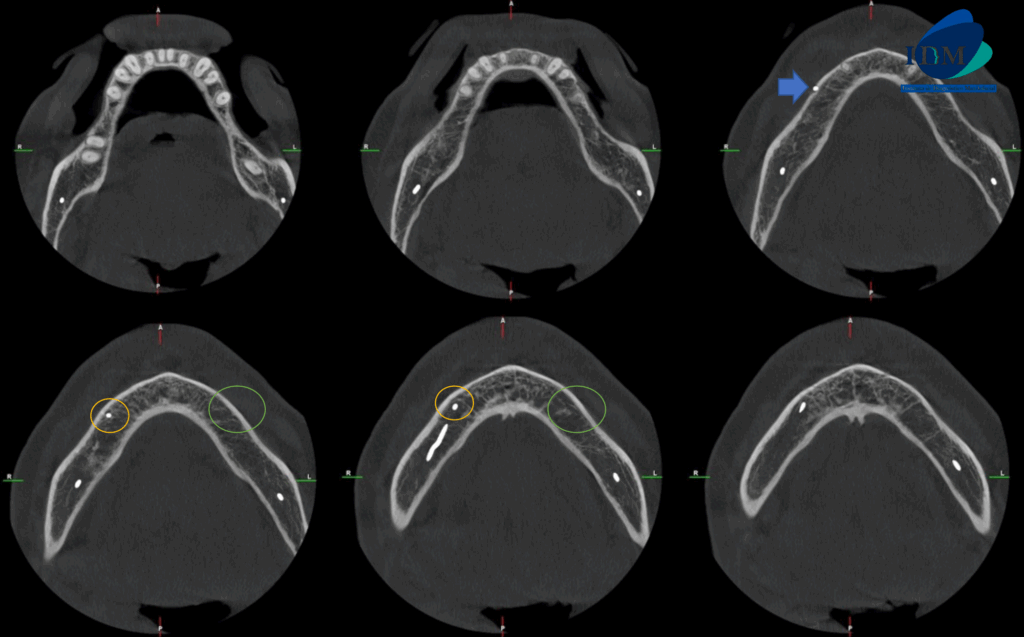

A la evaluación de la tomografía computarizada en vistas axiales, sagitales y coronal se puede observar la ausencia del agujero mentoniano del lado izquierdo y la continuidad de la tabla ósea vestibular en zona de premolares, sin embardo si se observan conductos incisivos vestibulares.

CORTES AXIALES